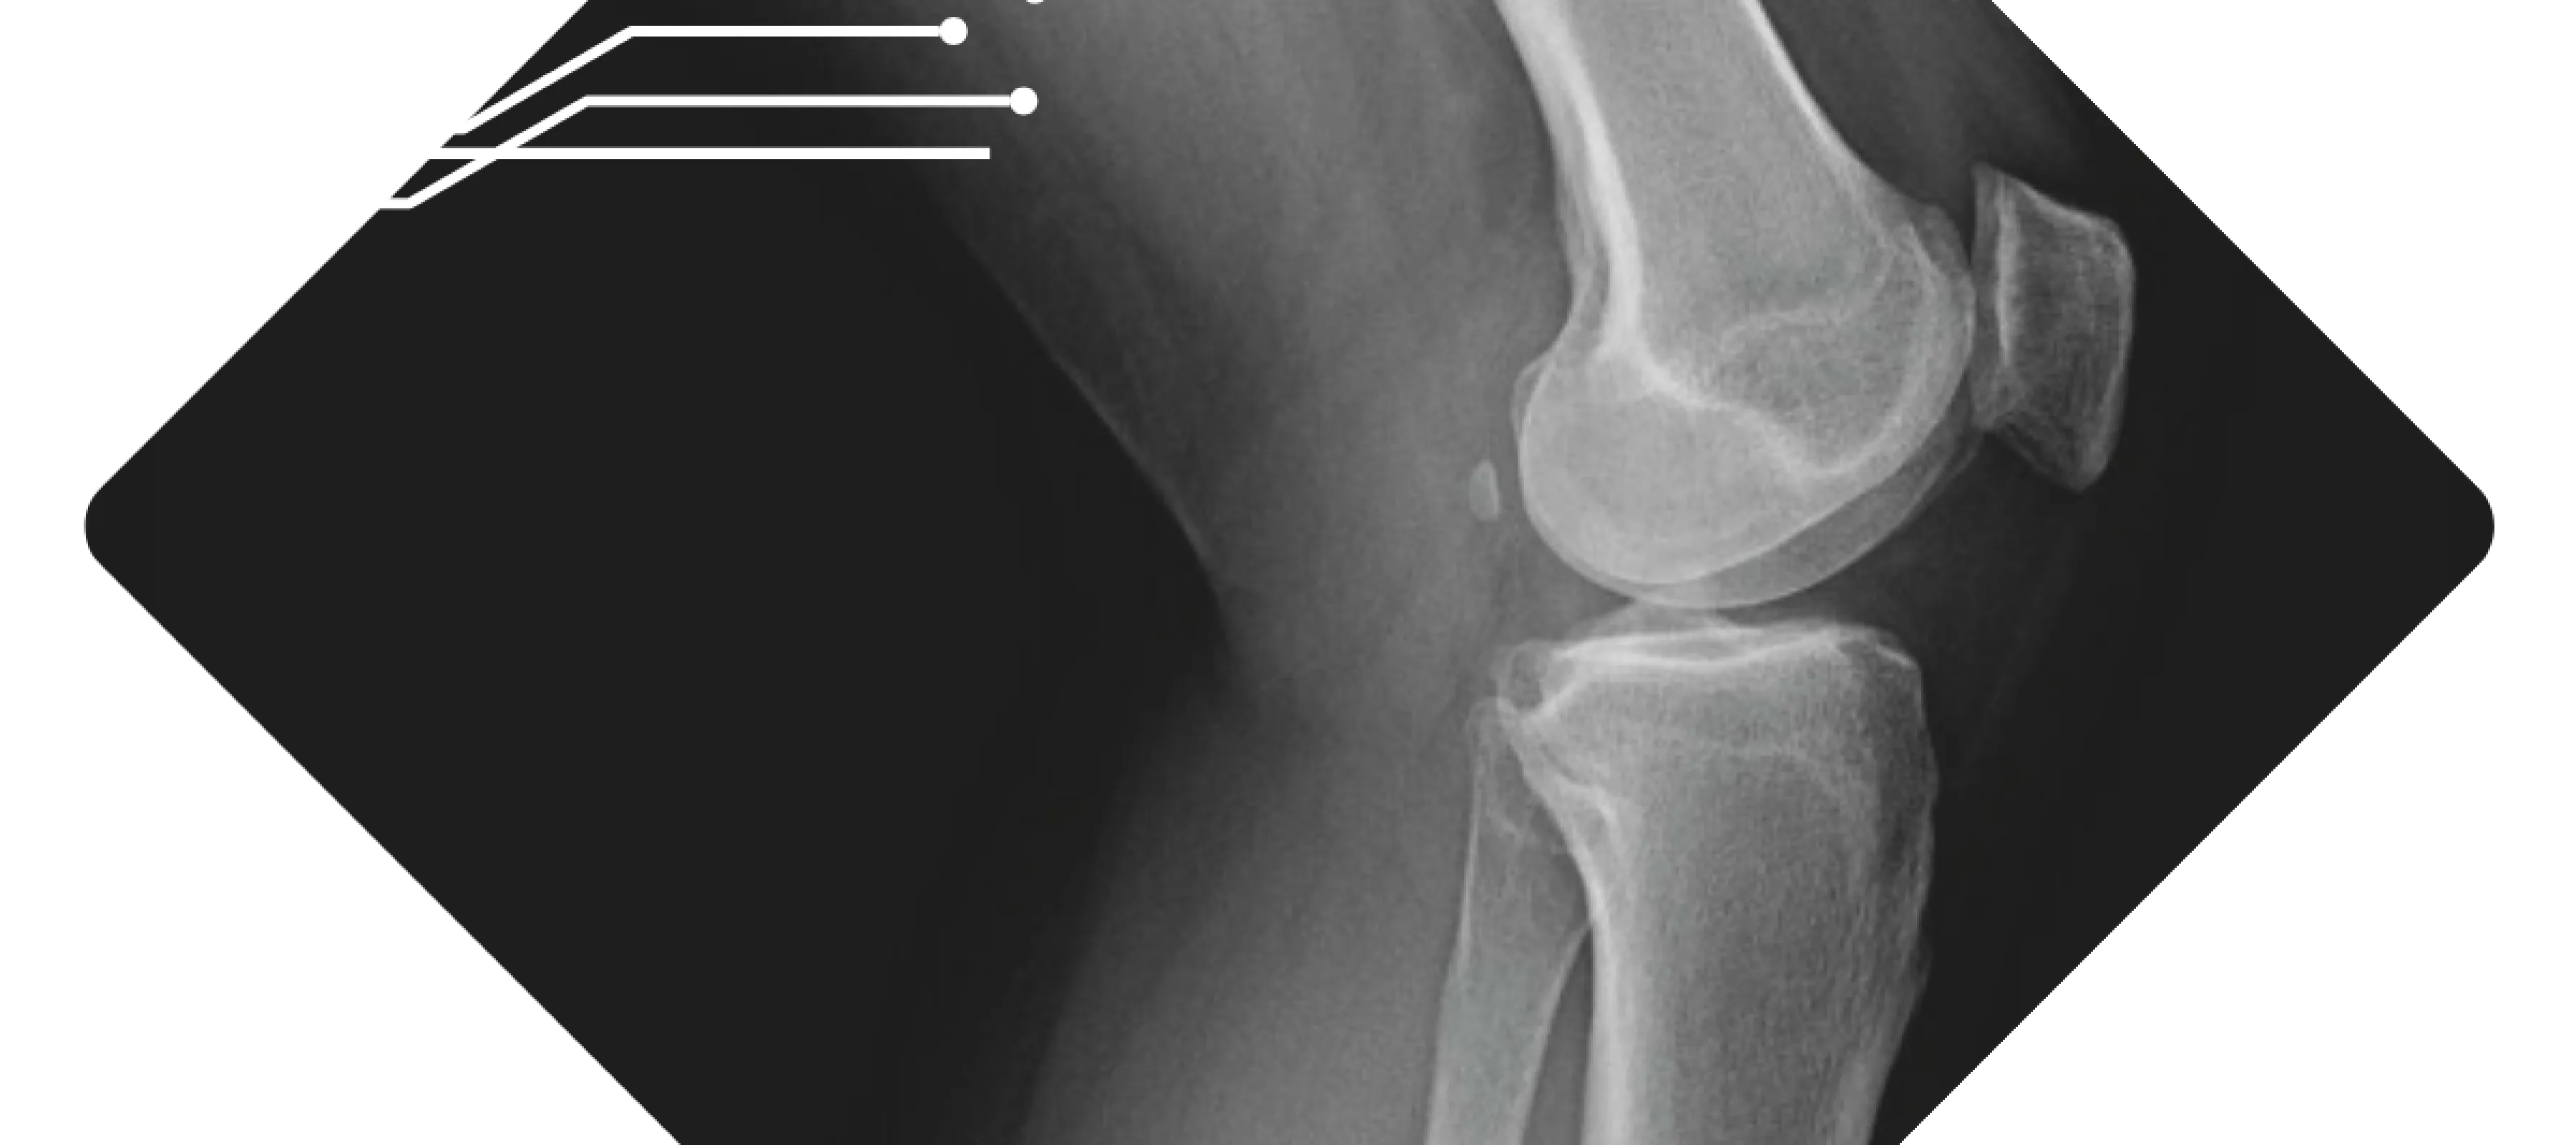

X-ray image showing a human knee joint with visible femur, tibia, and patella bones in a diamond frame.

We believe that the sooner you have answers, the sooner you can heal. Our practice maintains both digital X‑ray and mini‑fluoroscopy machines on‑site, which means we can capture high‑quality images during your appointment without sending you elsewhere. These machines are designed to deliver low‑dose radiation while providing clear, detailed images of bones and joints.

At our practice, your images are reviewed right away so you can talk through the findings and next steps before you head home. In orthopedics across the United States, requesting an X‑ray before your visit is considered standard care. It allows our specialists to see your bones and joints clearly and makes the best use of your time when you come in. We understand some people feel uneasy about imaging, but it's a routine part of musculoskeletal care that's focused on getting you the most accurate evaluation. If you are pregnant or scheduling an appointment for a child, please let us know; we'll coordinate with your doctor and take any extra precautions needed to keep you safe.

At Pacific Crest Orthopedics we have both X-ray and fluoroscopy machines in the office for quick diagnosis and evaluation of all orthopedic injuries. The machines are low radiation and give high-quality images. We can take immediate X-rays of most orthopedic injuries including injuries to the clavicle, shoulder, elbow, wrist, hand, finger, hip, femur, knee, tibia/fibula, ankle, and foot. Each of these can be taken during your appointment and then read promptly by the provider for an efficient diagnosis.

At Pacific Crest Orthopedics, we have advanced X-ray machines right here in our office that use very low radiation to produce clear, detailed images of your bones and joints. We can take X-rays of many areas, including your collarbone, shoulder, elbow, wrist, hand, fingers, hip, thigh, knee, shin, ankle, and foot, all during your appointment. This allows your doctor to quickly review the images and provide an accurate diagnosis so treatment can begin promptly.